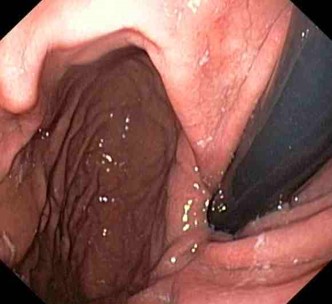

Magenspiegelung (Ösophago-Gastro-Duodenoskopie)

Zur Abklärung von Oberbauchbeschwerden, Schluckbeschwerden, Sodbrennen etc.

Testung auf Helicobacter pylorii

Endoskopische Entfernung von PEG Sonden (MagenSonden)

Endoskopische Tumornachsorge

CED-Patienten (chronisch entzündliche Darmerkrankungen), Morbus Crohn, Colitis ulcerosa

Tumornachsorge bei Patienten mit Magen-, Darm und Speiseröhrentumoren